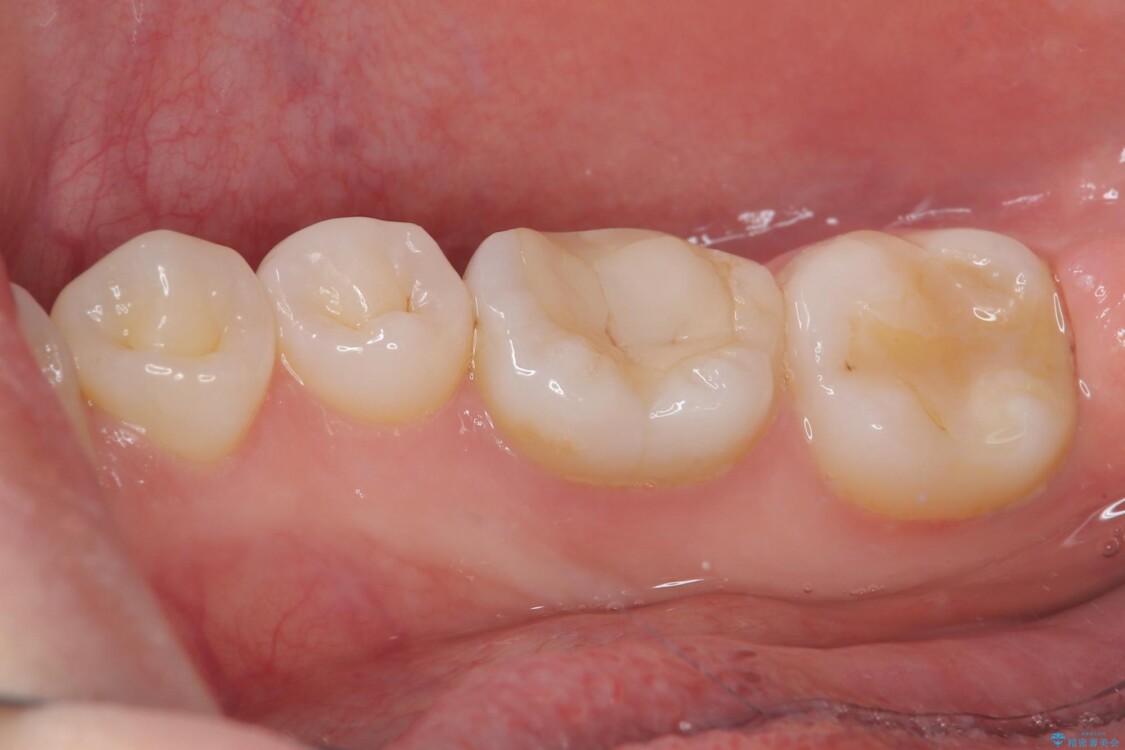

治療前

• ラバーダム使用で再感染リスクを抑えた再根管治療+精密な補綴による長期安定を実現 治療前画像